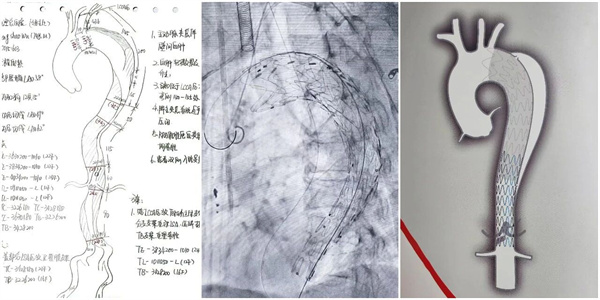

手术实施:两枚覆膜支架实现血运重建

在麻醉科的严密监护下,介入中心团队经股动脉入路,将覆膜支架精准输送至目标位置。首次释放支架覆盖主要破口后,造影显示真腔恢复,腹腔分支血流改善,但远端仍存在内漏。团队果断调整方案,续接第二枚覆膜支架,最终实现破口完全封闭,内漏消失;整台手术历时约90分钟。患者血流动力学保持平稳,术后安全返回重症医学科。

本例手术是医院首次对合并Stanford A型壁间血肿的主动脉夹层实施介入治疗,成功探索了该类高危病变的微创治疗新路径。其核心经验在于:通过多学科紧密协作与动态影像评估准确把握治疗时机;借助三维CT图像实现术中精准导航;依托覆膜支架技术完成有效的血运重建。主动脉夹层病情瞬息万变,尤其是Stanford A型病变,对医院的快速响应、多学科协作及介入技术水平提出了极高要求。